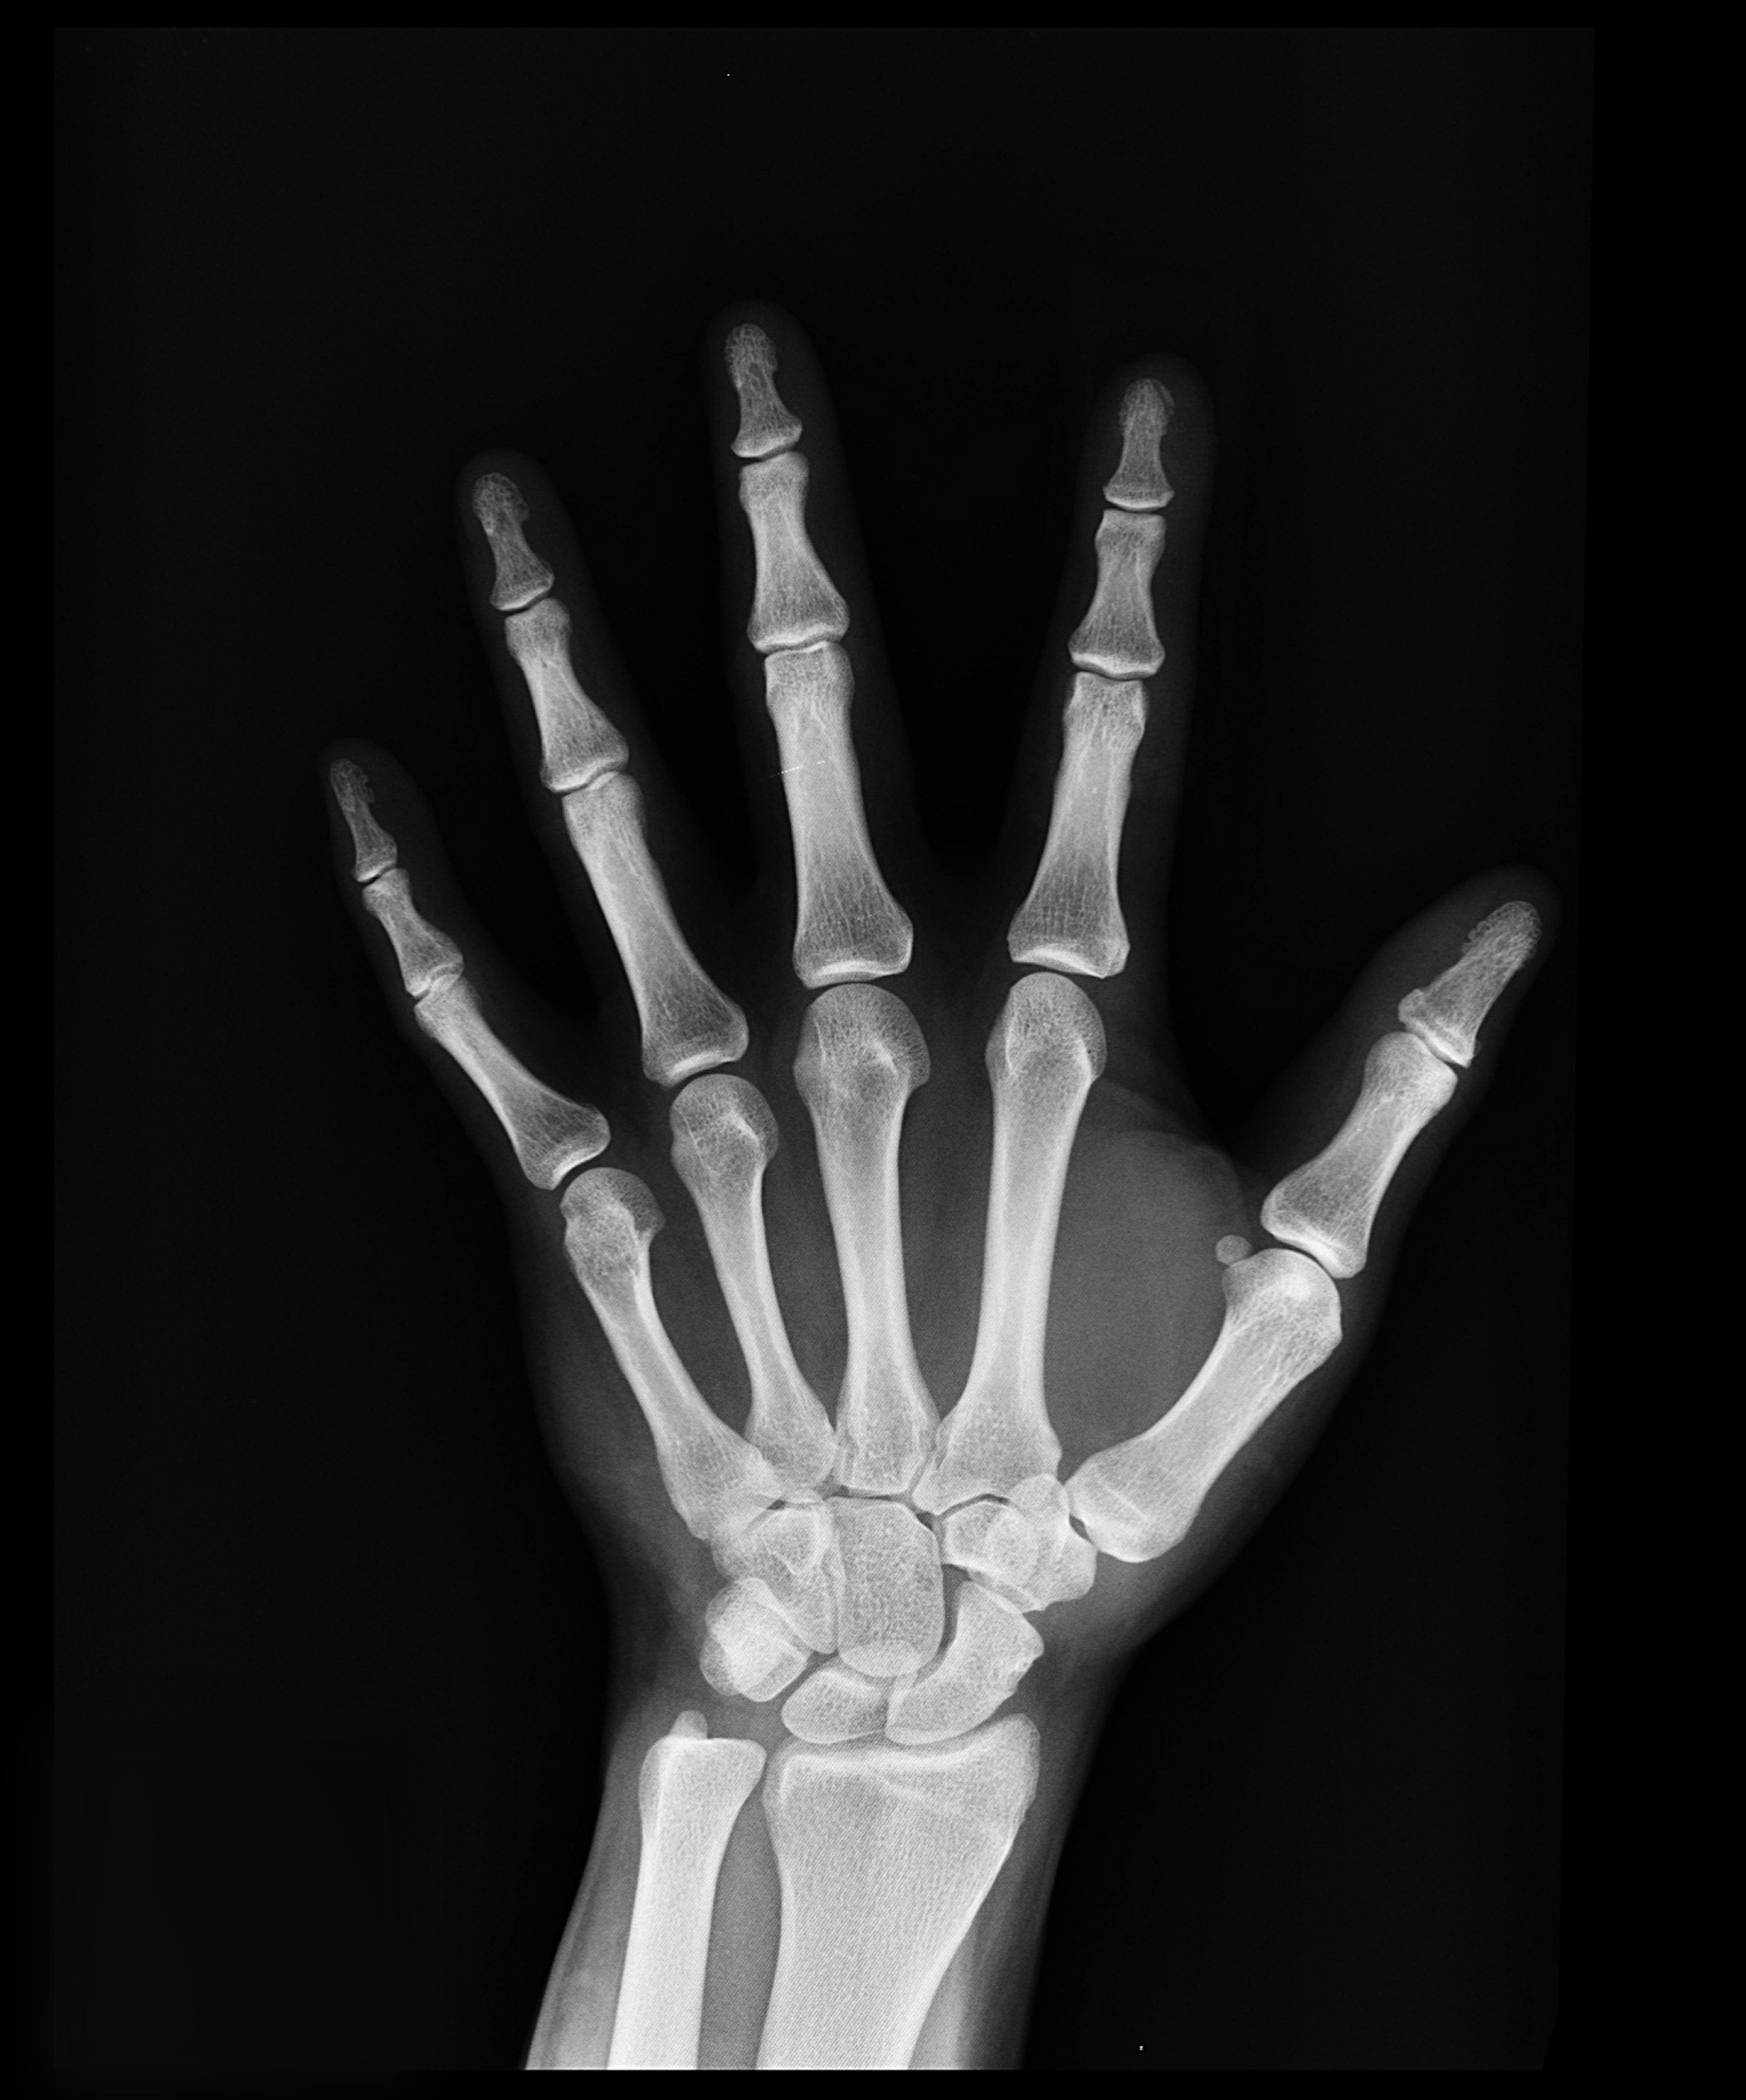

뼈는 신체의 기둥 역할을 하는 구조 기관이자, 혈액세포 생성과 미네랄 저장, 산염기 균형 유지 등 다양한 생리 기능을 수행합니다. 항산화 관점에서 뼈 건강을 이해하면, 골밀도 저하와 조직 손상 예방에 보다 효과적으로 접근할 수 있습니다.